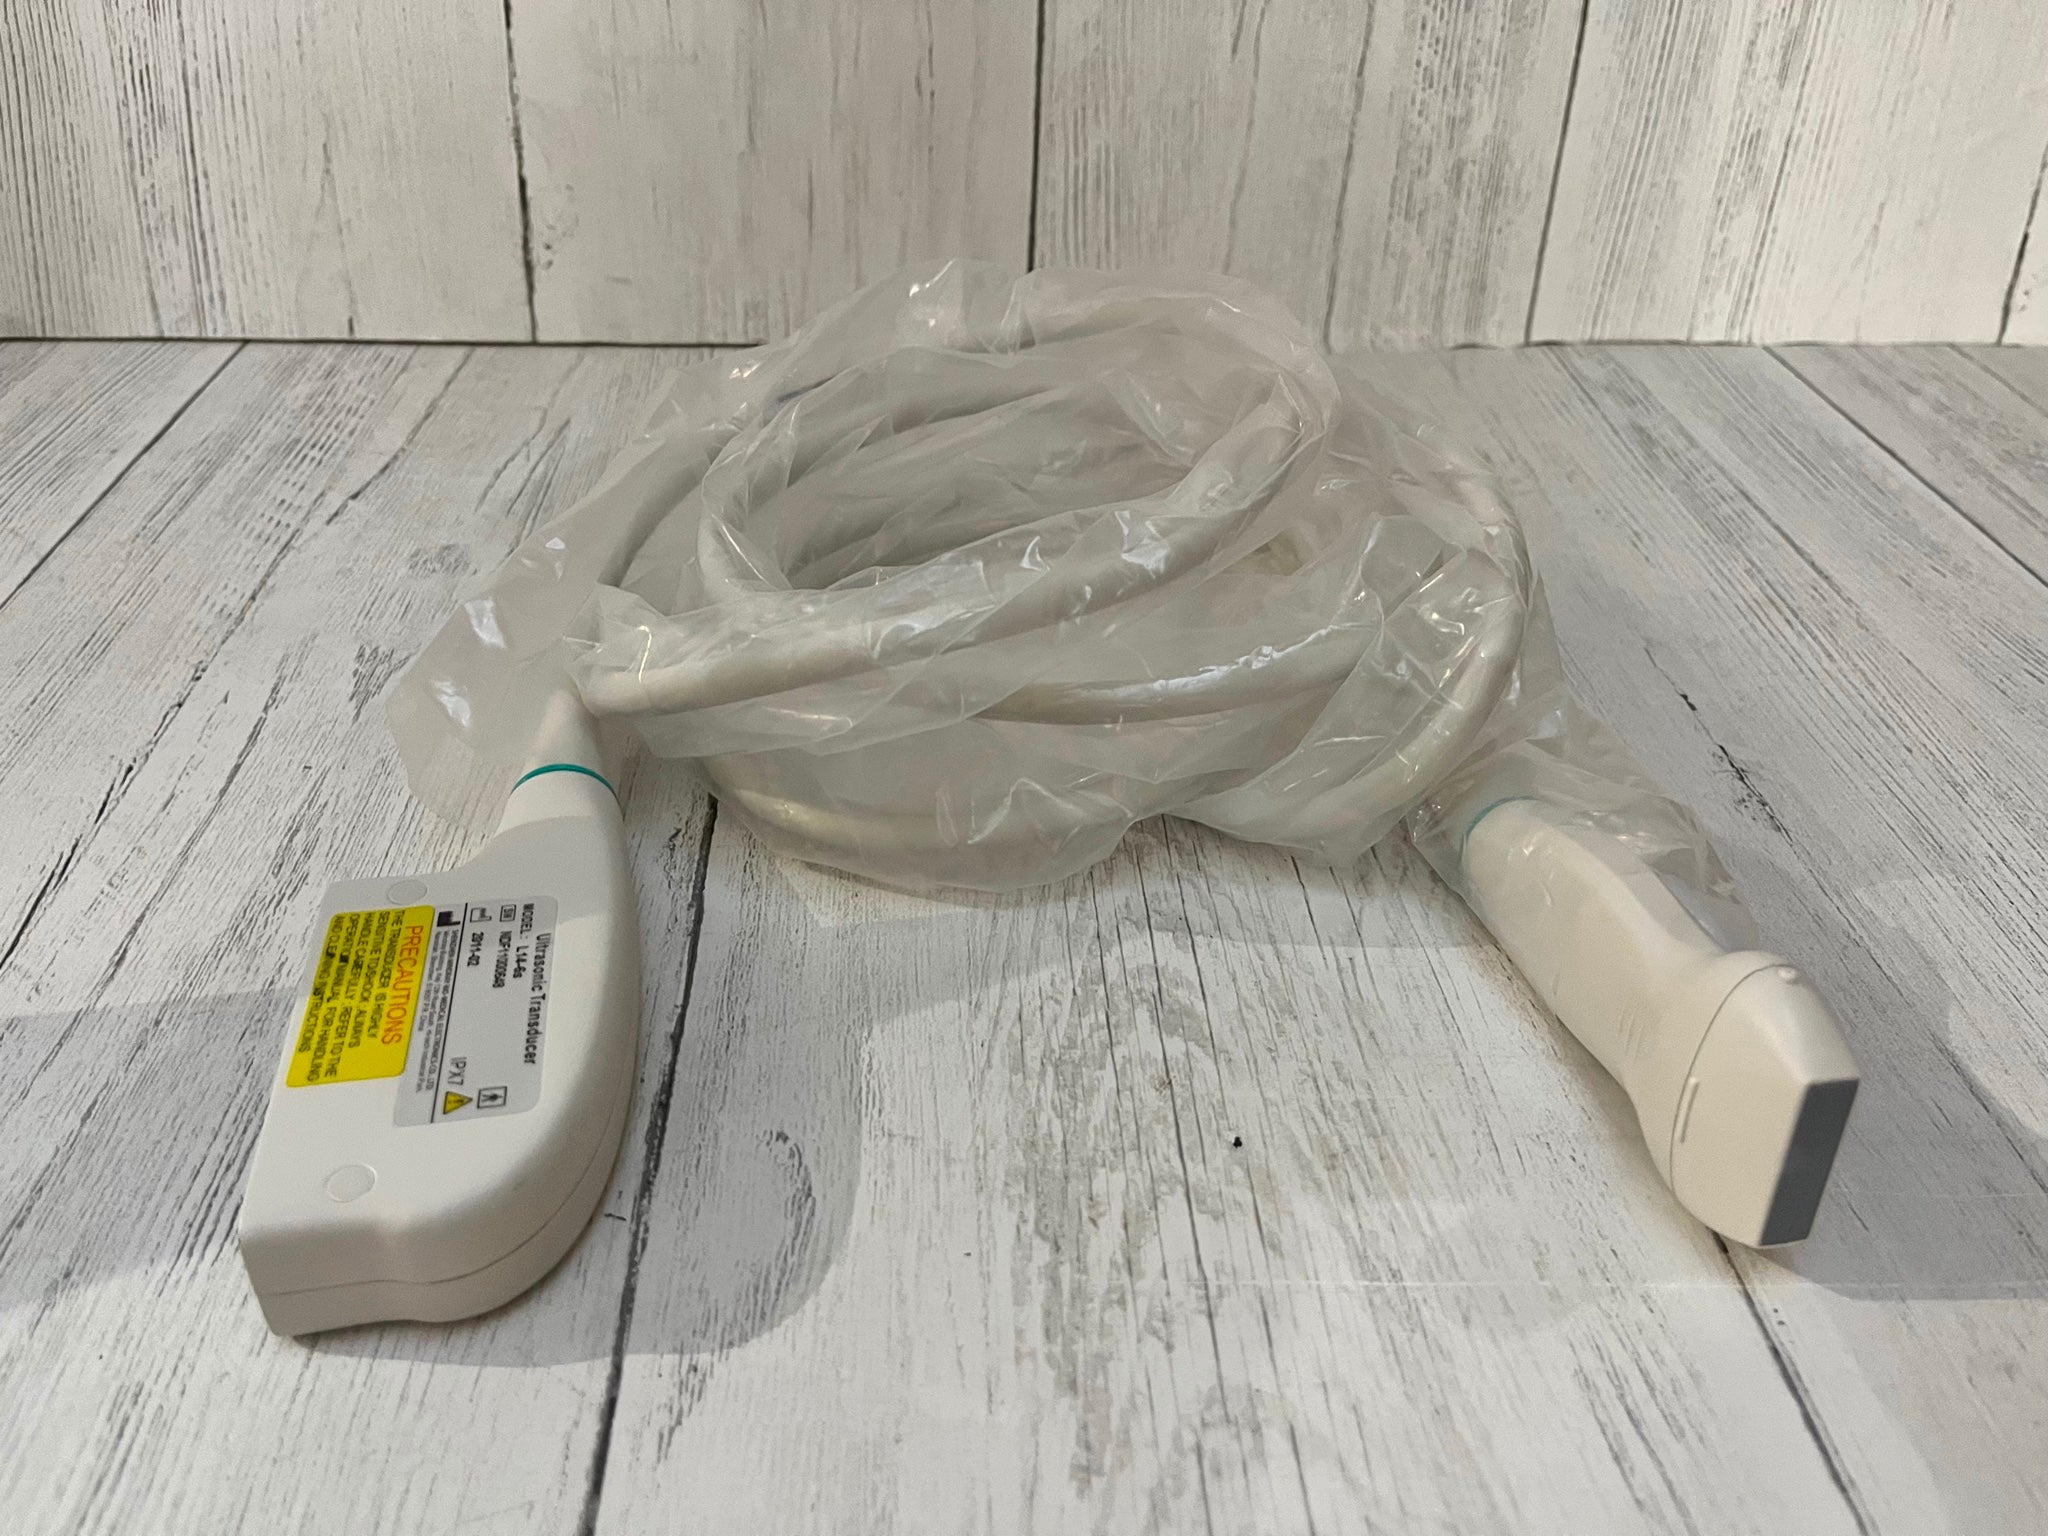

The Sonosite M-Turbo Portable is compatible with a wide range of probes and transducers, enhancing its versatility across various medical disciplines. Whether it's for abdominal imaging, vascular assessments, or musculoskeletal evaluations, this ultrasound machine delivers precise and dependable images. Moreover, the device supports advanced imaging modes such as Color Doppler, M-Mode, and Power Doppler, providing comprehensive diagnostic options for practitioners.